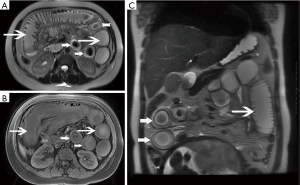

During treatment, 62 patients had follow up MRI examination, 16 of whom (26%) had a gastrointestinal tract abnormality on follow up examination, significantly lower than that on the initial MRI (P<0.05) (Figures 3-7). The frequencies of gastrointestinal tract abnormalities for initial and follow-up MRI examination are shown in Table 3. The difference for the frequencies of stomach, duodenum, jejunum, ileum, ascending and descending abnormal changes between before and after the treatment had statistical significance (P<0.05). There was no difference of transverse colon and bowel dilatation before and after the treatment (P≥0.05).

It was found that gastrointestinal tract wall thickness was greatly thinner after treatment (P<0.05) (Table 4).

In the follow-up MRI exam, the structure of gastrointestinal tract restored to revert in MRI, coinciding with relief of abdominal pain, recovered appetite, cessation of hematuria, amylase recovery and anal passing gas.

We noted two patterns of wall enhancement in the initial exam; diffuse, and stratified. Tolan et al. (29) proposed that the patterns of wall enhancement could help determine the likely level of disease activity. Tolan et al. reported that stratified enhancement was observed in combination with submucosal edema in active disease and that diffuse enhancement commonly represented transmural inflammation. Low-level inhomogeneous enhancement was often observed in fibrosis (22). We consider that the wall thickening we observed with AP resulted from active inflammation, and that this inflammation was transmural in some cases. In the follow-up examination, we noted smooth mild wall thickening with no mural stratification, confirming that active inflammation could resolve soon after treatment.